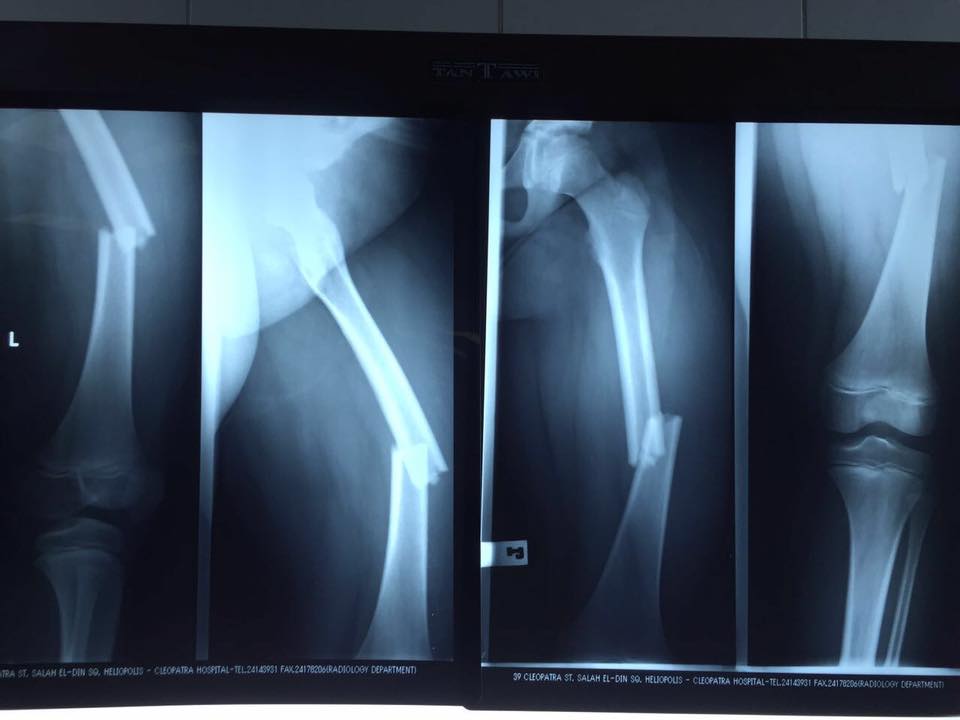

Apparently the lack of safety guides and poorly-designed slide has risked her son’s life. After her child fell off and broke his leg, the owner of the slide paid them a visit at the hospital and insinuated that her child was not the first victim of the slide. Perhaps she could have seeked support from a personal injury lawyer for legal guidance on her son’s injuries, and check out https://www.noll-law.com/il/springfield-personal-injury-lawyer/ for more information on the case. How many people have to get insulted, injured and killed in this country for actions to be taken? Can we just once prepare ourselves for the worst without waiting for a disaster to happen and go viral?